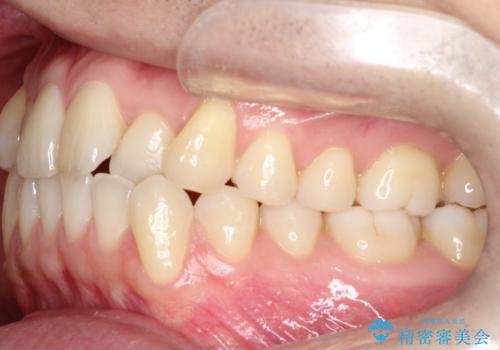

- 前歯の凸凹を主訴に来院されました。

マウスピース矯正も適応でしたが、ワイヤー矯正を希望され治療を行なっております